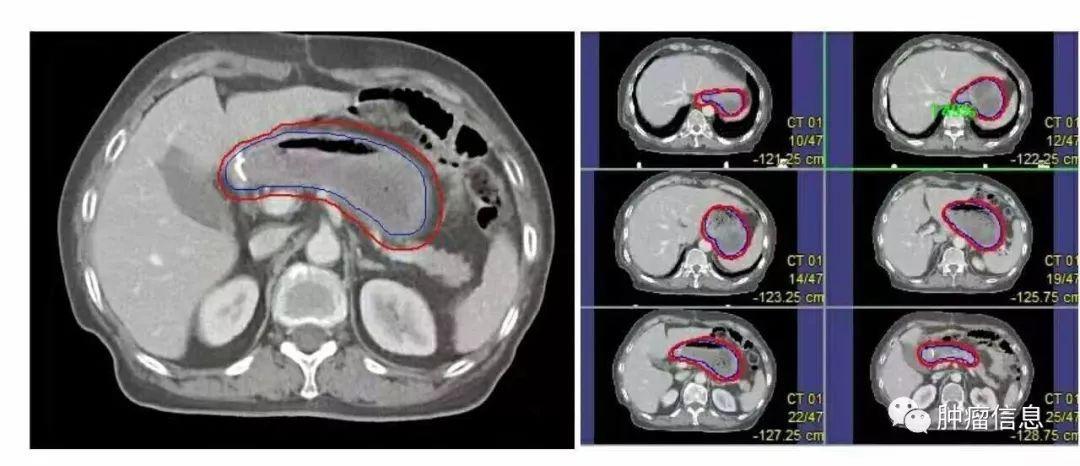

No.16腹主动脉旁淋巴结

上界:腹腔干上缘下界:L3下缘(肠系膜下动脉上缘)